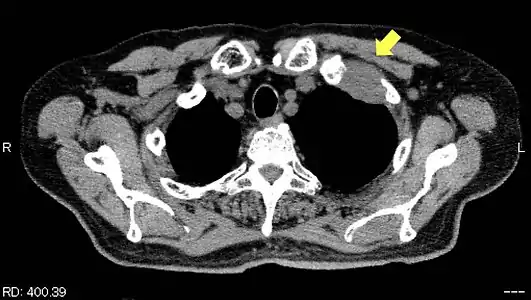

TDM d'une tumeur de Pancoast gauche envahissant l'arc antérieur de la 1re et de la 2e côte (flèche jaune).

TDM d'une tumeur de Pancoast gauche envahissant l'arc antérieur de la 1re et de la 2e côte (flèche jaune). PET-scanner du même patient[14].

Les côtes sont envahies de manière isolée chez 65 % des patients[15] ; seulement 8 % présentent un envahissement en bloc des côtes et des vertèbres adjacentes[15].

Tomodensitométrie

Le scanner thoracique permet d'analyser avec précision la localisation de la tumeur, de mesurer sa taille, et de rechercher des adénopathies médiastinales[11]. Idéalement, il doit être injecté d'un produit de contraste iodé afin de préciser les rapports vasculaires[11].